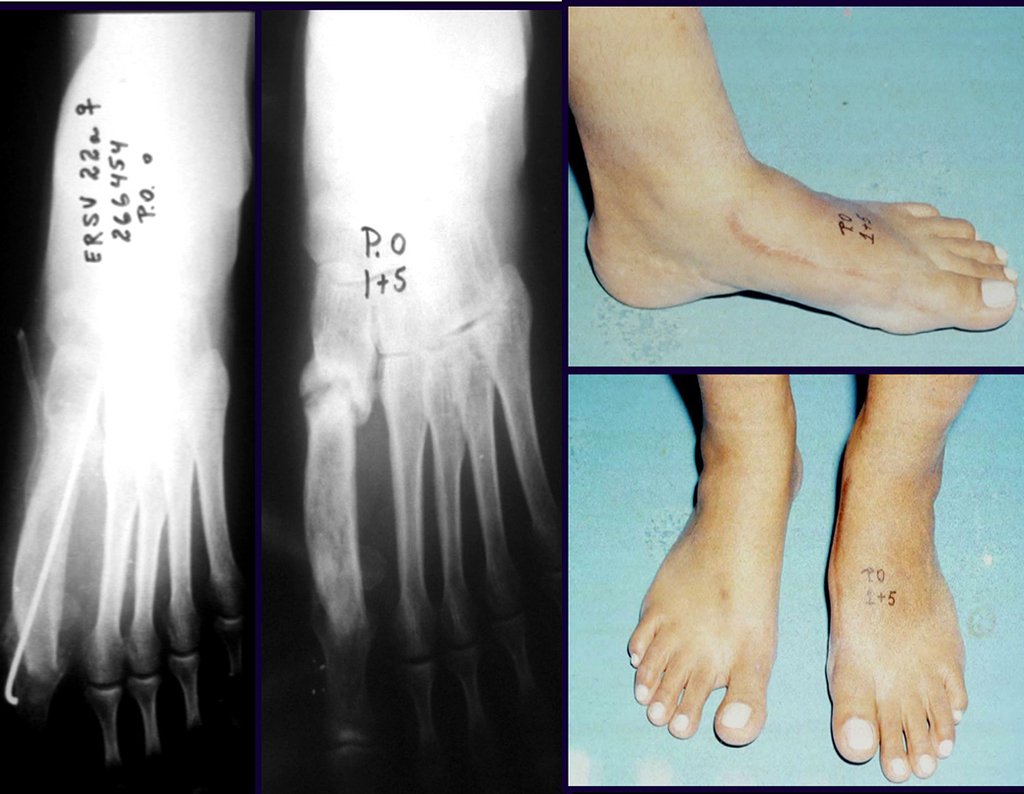

El peroné también se puede utilizar vascularizado en reconstrucciones, incluso con la placa de crecimiento para reemplazar la que será resecada debido al tumor. Se trata de un autotrasplante de peroné con la placa fisaria, realizándose osteosíntesis con el dispositivo de fijación interna extensible, figuras 63 y 64.

En la reconstrucción de pequeños segmentos, como en la reconstrucción del radio, por traumatismos o tumores, podemos utilizar el peroné libre con buenos resultados, figuras 65 y 66.